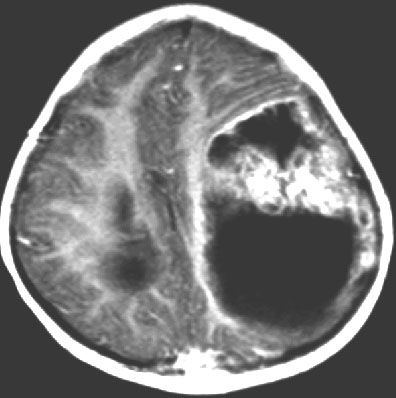

2歳の子どもの例

2歳の時に右の片麻痺と意識障害で発症しました。手術できれいにとれて,20年経ちますが再発はありませんし,運動麻痺もありません。この画像を見ると左の一次運動野が侵されていて,麻痺が治るということは信じられないのですが,2歳以下の小さな子どもの麻痺は治ることがあります。乳幼児のこの腫瘍は積極的な摘出を行った方がいいでしょう。

- 大脳の表面にできて,とても大きな腫瘍で,大きなのう胞(液体がたまる)を伴います

- 液体のたまっているのう胞が大部分です

- 不正形に造影剤で増強されて白く映る塊が見えますが,それが本体です

- 頭頂葉と前頭葉表面に広がり数センチを越える巨大なのう胞性腫瘍となります

- 大脳深部方向へ食い込むのう胞があり,固形腫瘍部分は結節様に表在することが多いです

- 石灰化は珍しく,一部がガドリニウム増強されます